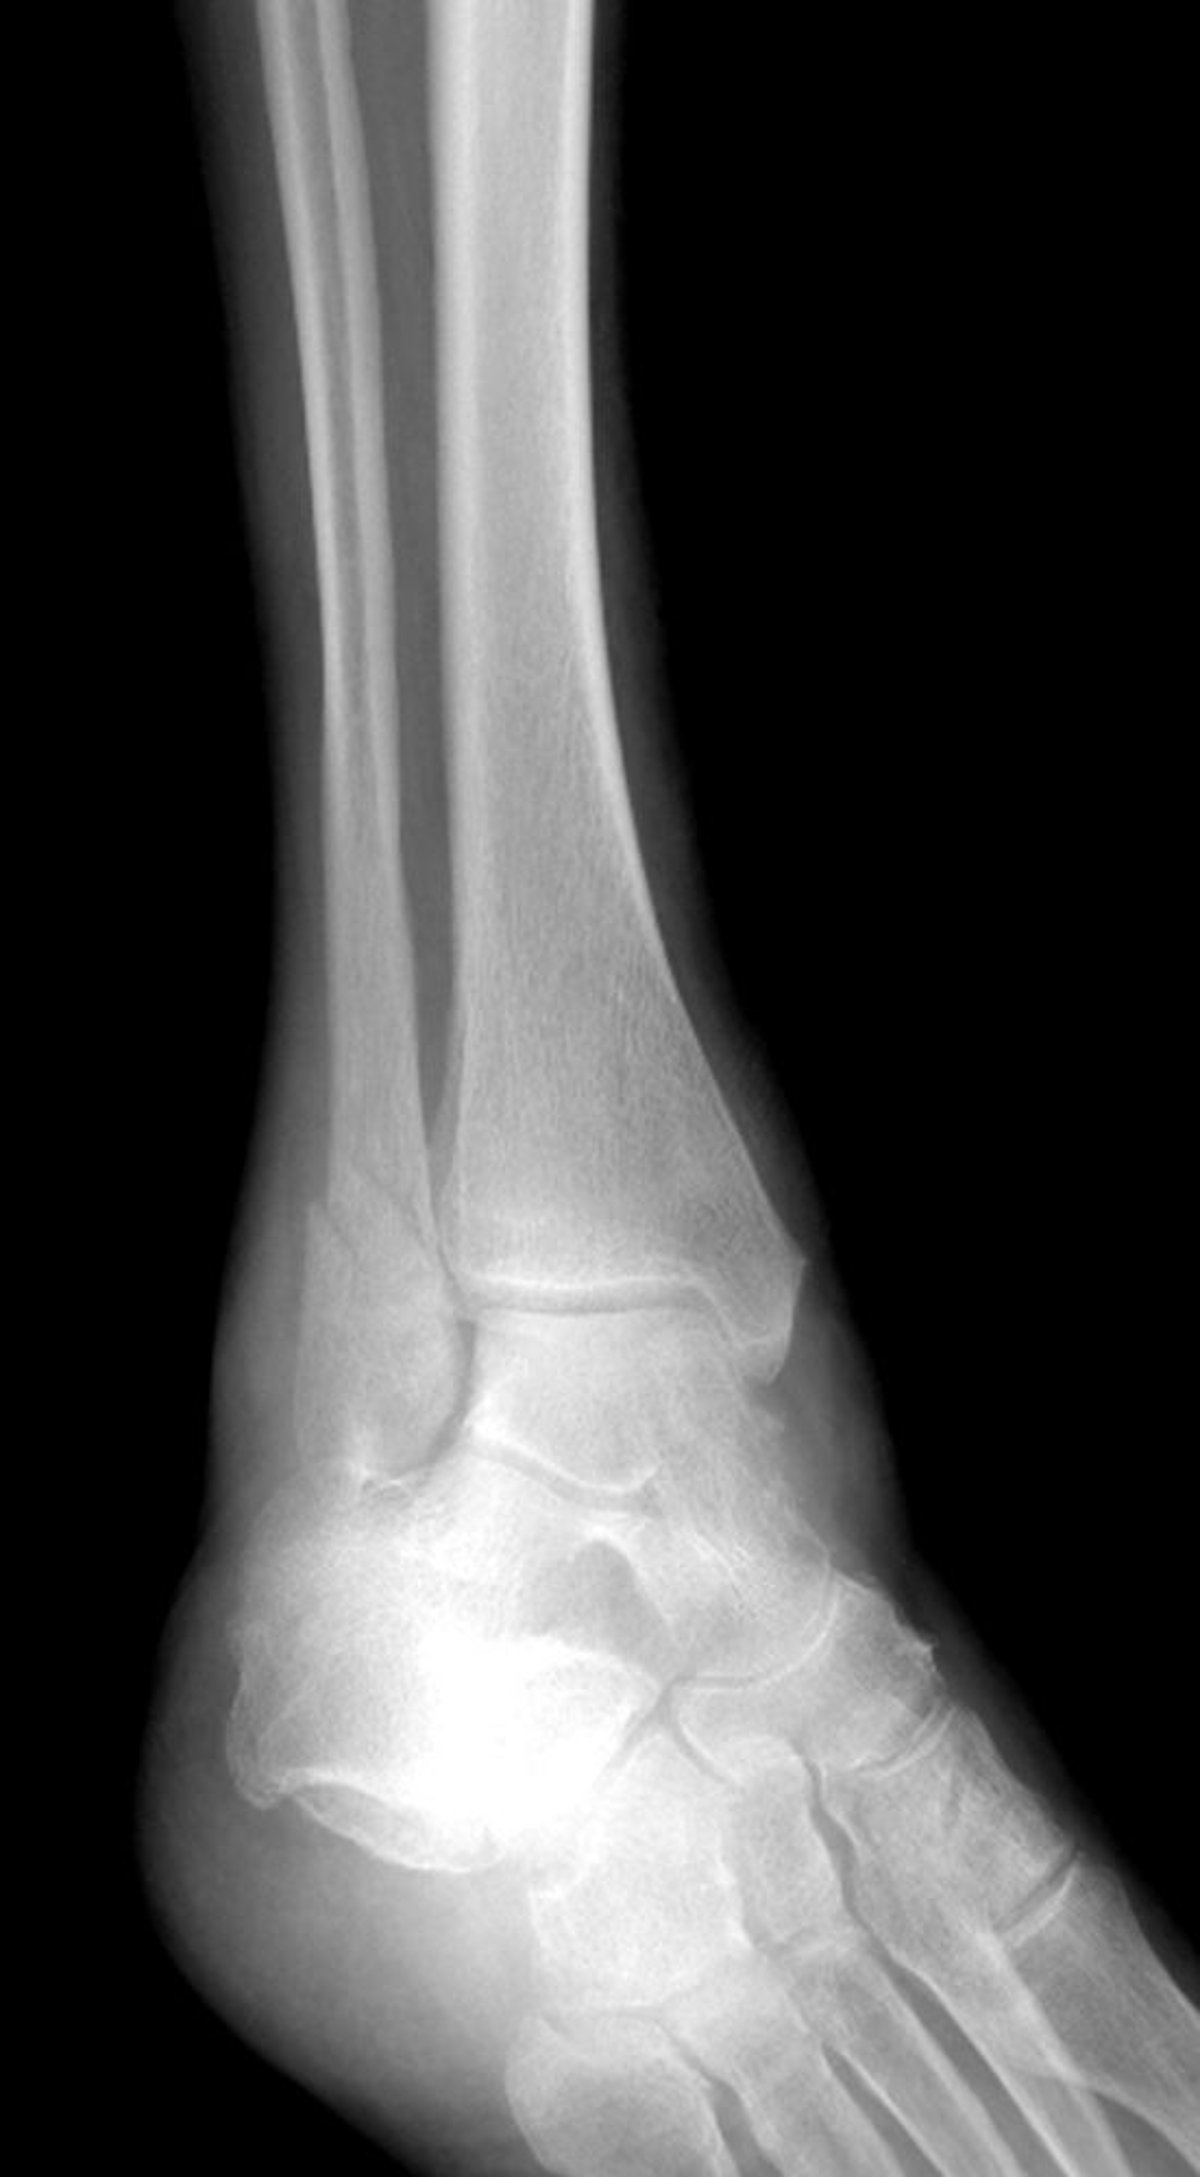

Gãy mắt cá ngoài

Vết gãy xương cổ chân này gây tổn thương mắt cá ngoài nhưng không ảnh hưởng đến mắt cá trong.